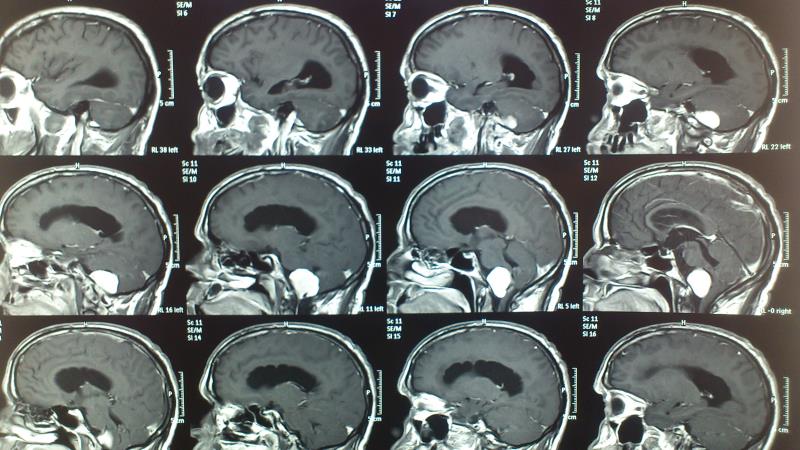

Ασθενής  άνδρας 55 ετών  προσήλθε λόγω αστάθειας βάδισης  και πάρεσης  των κατώτερων εγκεφαλικών συζυγιών  ( ΙΧ,Χ,ΧΙ ). Ο  έλεγχος με μαγνητική τομογραφία εγκεφάλου ανέδειξε εικόνα συμβατή  με μηνιγγίωμα ινιακού τρήματος με σημαντική πίεση επί του στελέχους. Ο ασθενής υποβλήθηκε σε αριστερή  Far Lateral Transcondylar προσπέλαση. Μετεγχειρητικά ο ασθενής παρουσίασε ήπια επιδείνωση της πάρεσης των κατώτερων εγκεφαλικών συζυγιών που ωστόσο αποκαταστάθηκε σταδιακά στα προεγχειρητικά επίπεδα Ο μετεγχειρητικός απεικονιστικός έλεγχος ανέδειξε ολική αφαίρεση του όγκου.

Προεγχειρητικός απεικονιστικός έλεγχος